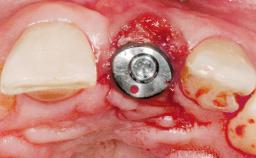

Late Placement of an Implant in a Maxillary Left Central Incisor Site

A 36-year-old female patient was referred for the replacement of the upper left central incisor (tooth 21), which had fractured. Although the tooth had been asymptomatic for many years, the crown began to loosen, at which time she presented to her dentist for an assessment. Teeth 21 and 22 had both been endodontically treated many years previously. She was a healthy individual and a non-smoker.

Bone Augmentation Horizontal|Staged

Augmentation Materials Xenogenous|Membrane

Bone Volume Deficient horizontally, requiring prior grafting